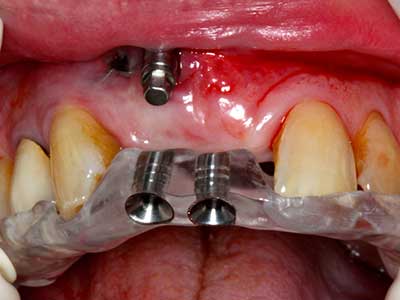

Fig. 13: Adequate irrigation with the 4-mm residual bone width is essential for this 52-year-old patient during the bone splitting.

Fig. 14: Placement of four tapered RSX implants (Bego Implant Systems, Bremen).

Fig. 15: The one-year follow-up x-ray examination shows stable conditions at the bone level.

Fig. 16: The intraoral conditions are also stable with embedding of the implants in keratinized gingiva.